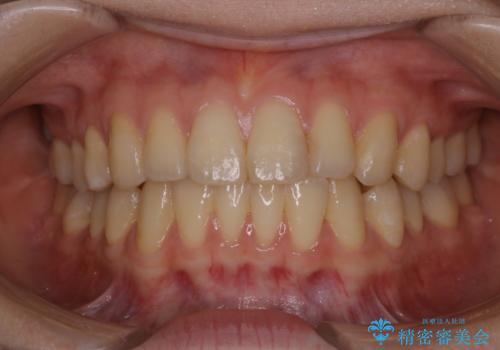

マウスピース矯正終了後にPMTCでよりきれいな歯に

- インビザラインでのマウスピース矯正が終了したため、きれいにクリーニングして口元を明るい印象にしたいとのことでした。PMTC60分コースを行いました。

矯正治療が終わり、せっかくきれいになった歯並びも、虫歯・歯周病などになってしまっては元も子もありません。

矯正治療やセラミックなどによる被せ物の治療終了のタイミングではクリーニングを行い、汚れや着色の除去、歯と歯の間・歯と歯肉との境目などのケアをしっかりすることをおすすめしています。